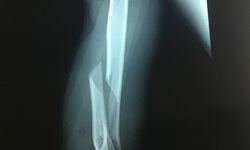

Camera bệnh viện - 12/04/2020 12:10SKĐS - Gãy xương cánh tay, đó là tai nạn bất ngờ mà anh Phạm Mạnh C. 19 tuổi trú tại Tiền An - Quảng Yên sau khi đọ sức cùng người bạn thông qua trò vật tay khiến anh phải đến BV Việt Nam – Thụy Điển Uông Bí cấp cứu.